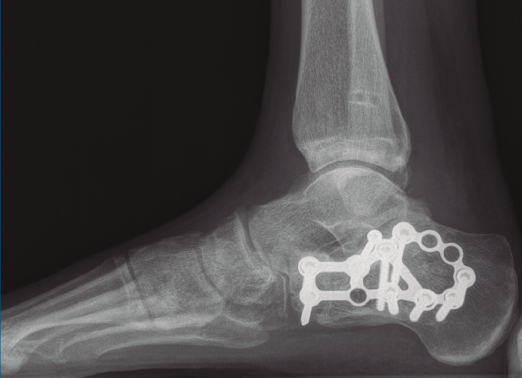

A los 9 meses únicamente presentó dolor ocasional al nivel de la articulación subastragalina y molestias en la planta del pie al deambular descalzo, por lo que se pauta plantilla amortiguadora, con la que mejora notablemente la sintomatología. Presentó una puntuación de 83 sobre 100 en la escala de la American Orthopaedic Foot and Ankle Society (AOFAS), ligeramente superior a la media descrita en estudios previos(2,3). Radiográficamente se evidenció una anatomía restablecida del calcáneo y de la sindesmosis, así como una altura adecuada de ambos tobillos (Figuras 12 y 13). Dada la buena evolución, se decidió continuar con el seguimiento anual del paciente sin realizar la extracción del material de osteosíntesis, para valorar la necesidad de una futura artrodesis subastragalina.

Figura 12. Radiografía de perfil a los 9 meses de la cirugía.